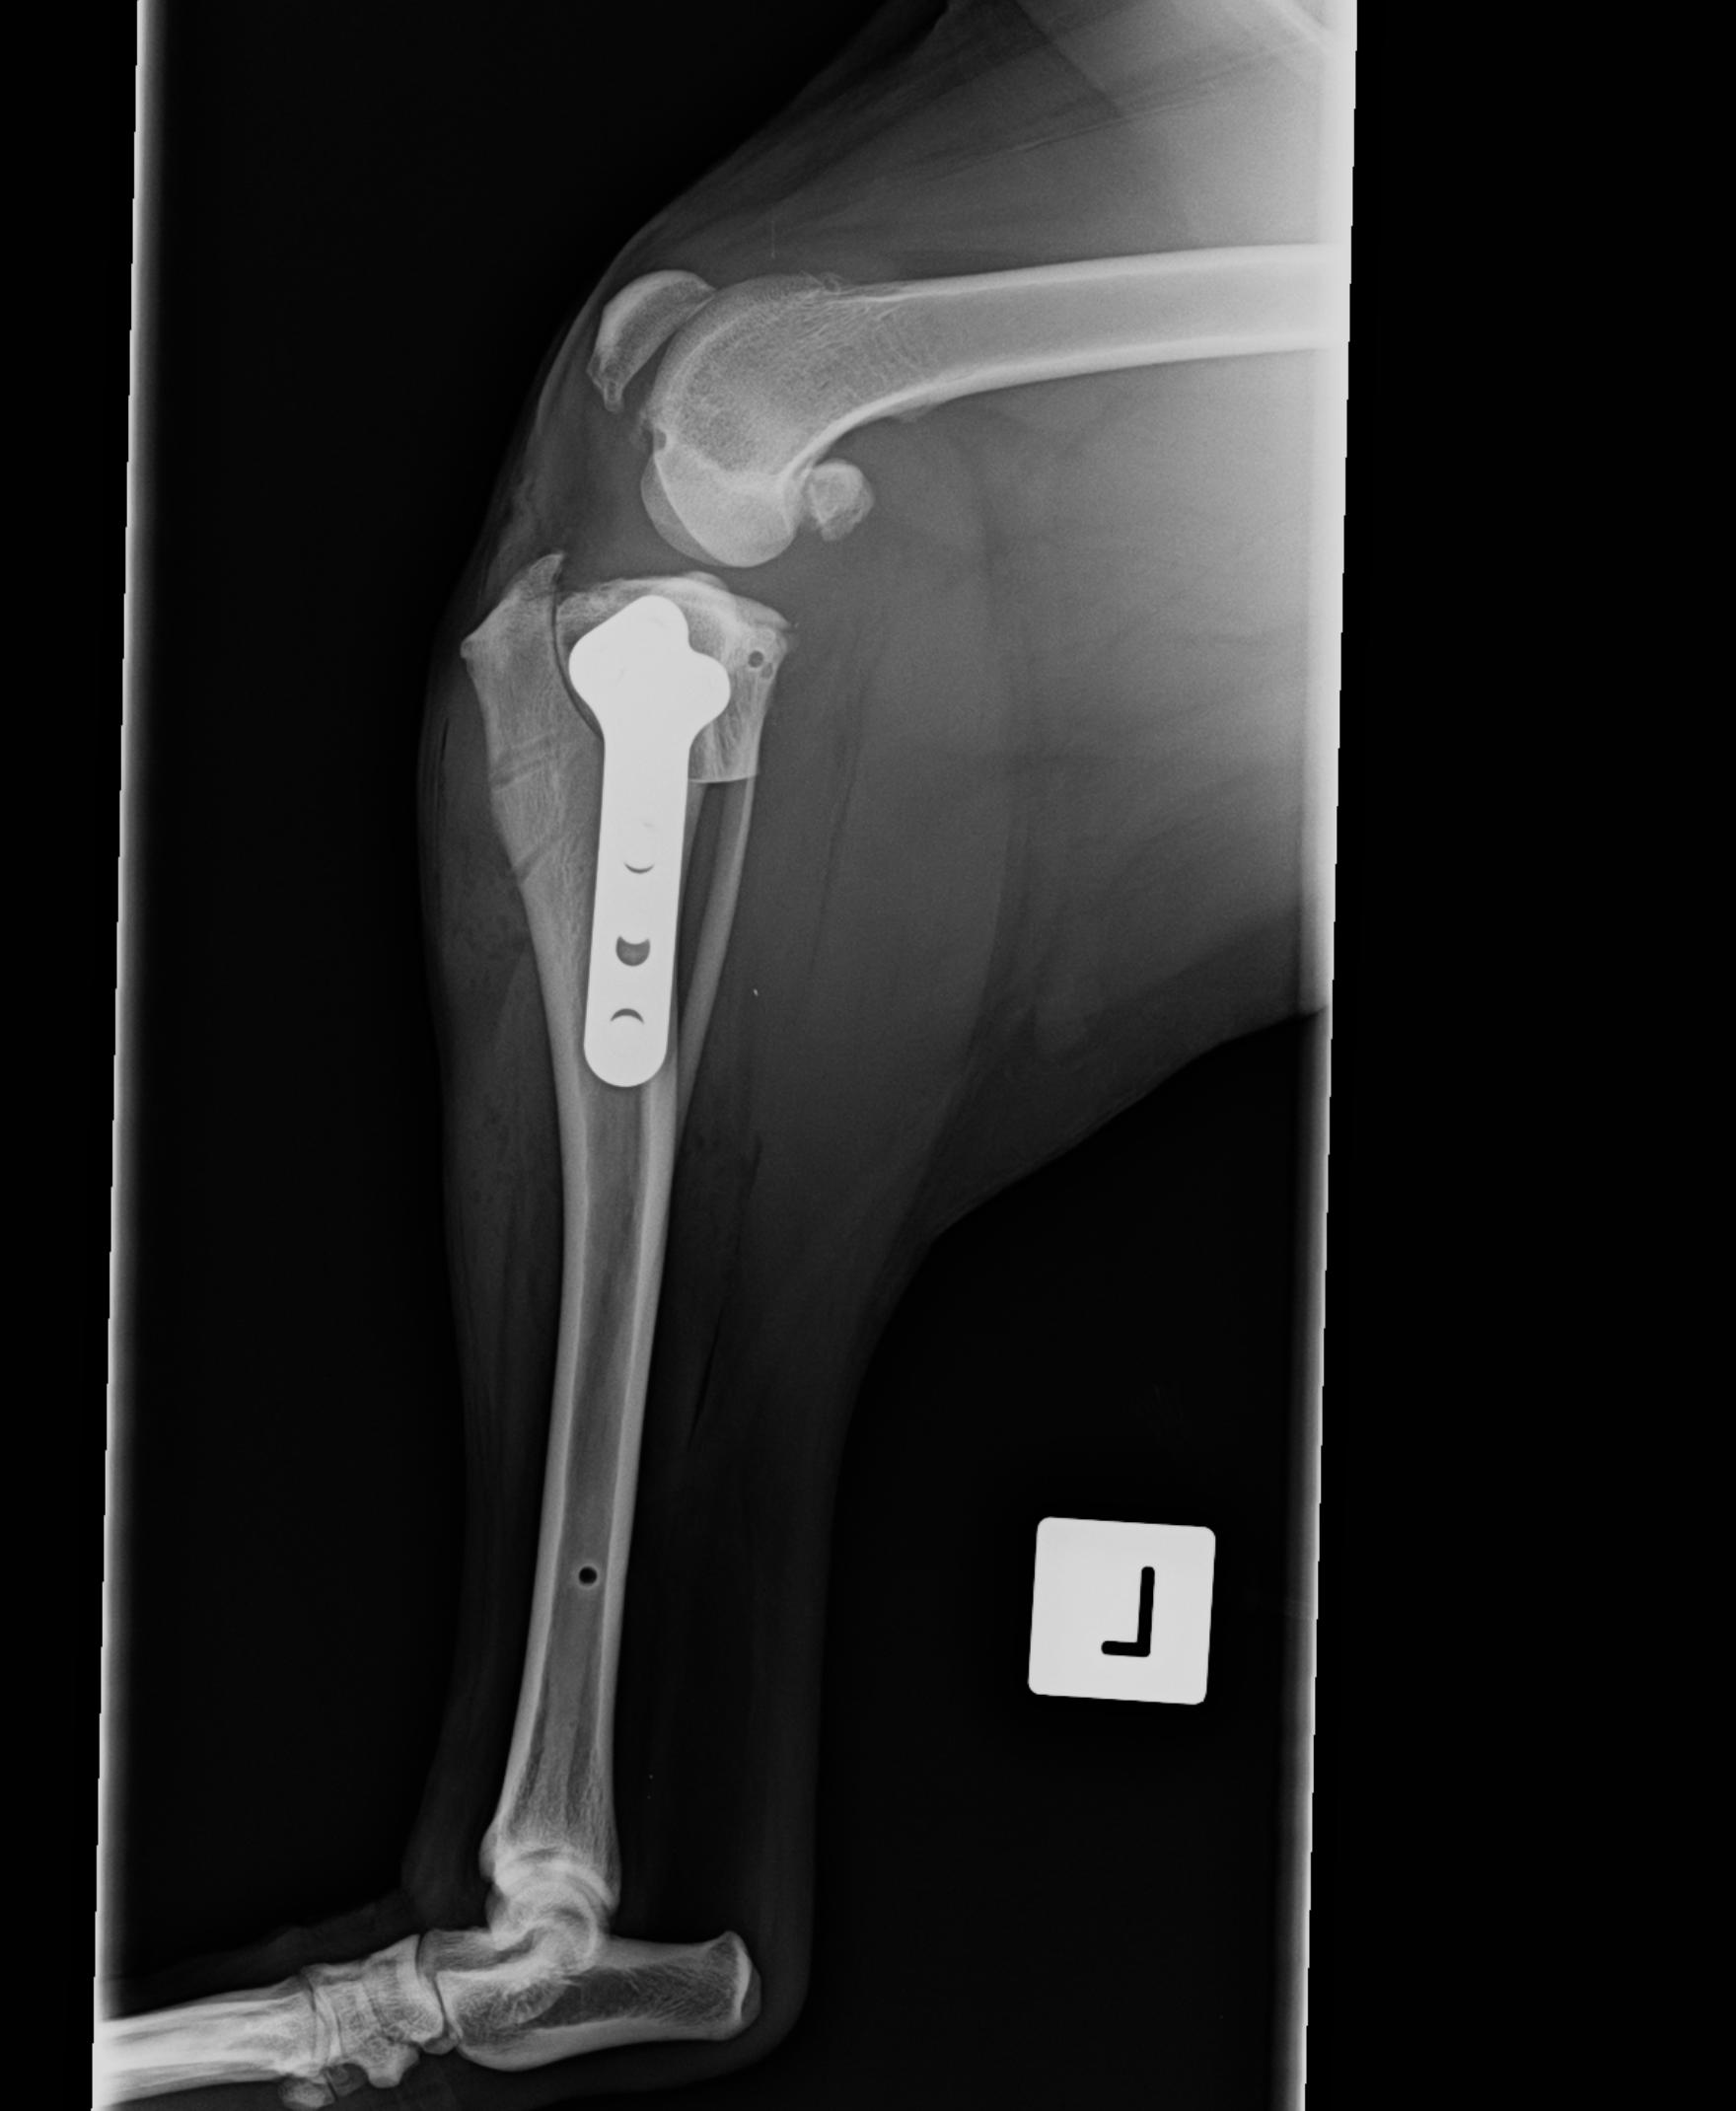

From www.advancedvetsurgery.com.au

Late meniscal Injury Medial Meniscus Injury Dog Cruciate Surgery Dog Knee Meniscus Tear In this article, we’ll learn what a torn acl (aka crcl) entails in dogs, as well as the signs, common causes and treatment options, explained by a vet. The meniscus can also degenerate over time. Learn about meniscal injury, a common problem in the stifle joint of dogs and cats, and how it is diagnosed and treated. Limping is often. Dog Knee Meniscus Tear.

Late meniscal Injury Medial Meniscus Injury Dog Cruciate Surgery Dog Knee Meniscus Tear The most common type of tear is the. Injuries usually involve the medial meniscus and typically occur following cranial cruciate rupture. In this article, we’ll learn what a torn acl (aka crcl) entails in dogs, as well as the signs, common causes and treatment options, explained by a vet. Limping is often the first sign of a cruciate problem. The. Dog Knee Meniscus Tear.